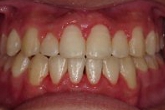

CASE2

↓前歯の歯並びを きれいに治したい。

(35歳/女性)

概要・担当医コメント:叢生・審美障害↑

動的治療期間13ヶ月(12回)/非抜歯/費用概算:55万円

上は固定式のブラケット矯正で,下は患者様ご自身が着脱するマウスピース矯正の治療を行いました.治療結果には大変満足されているそうです.